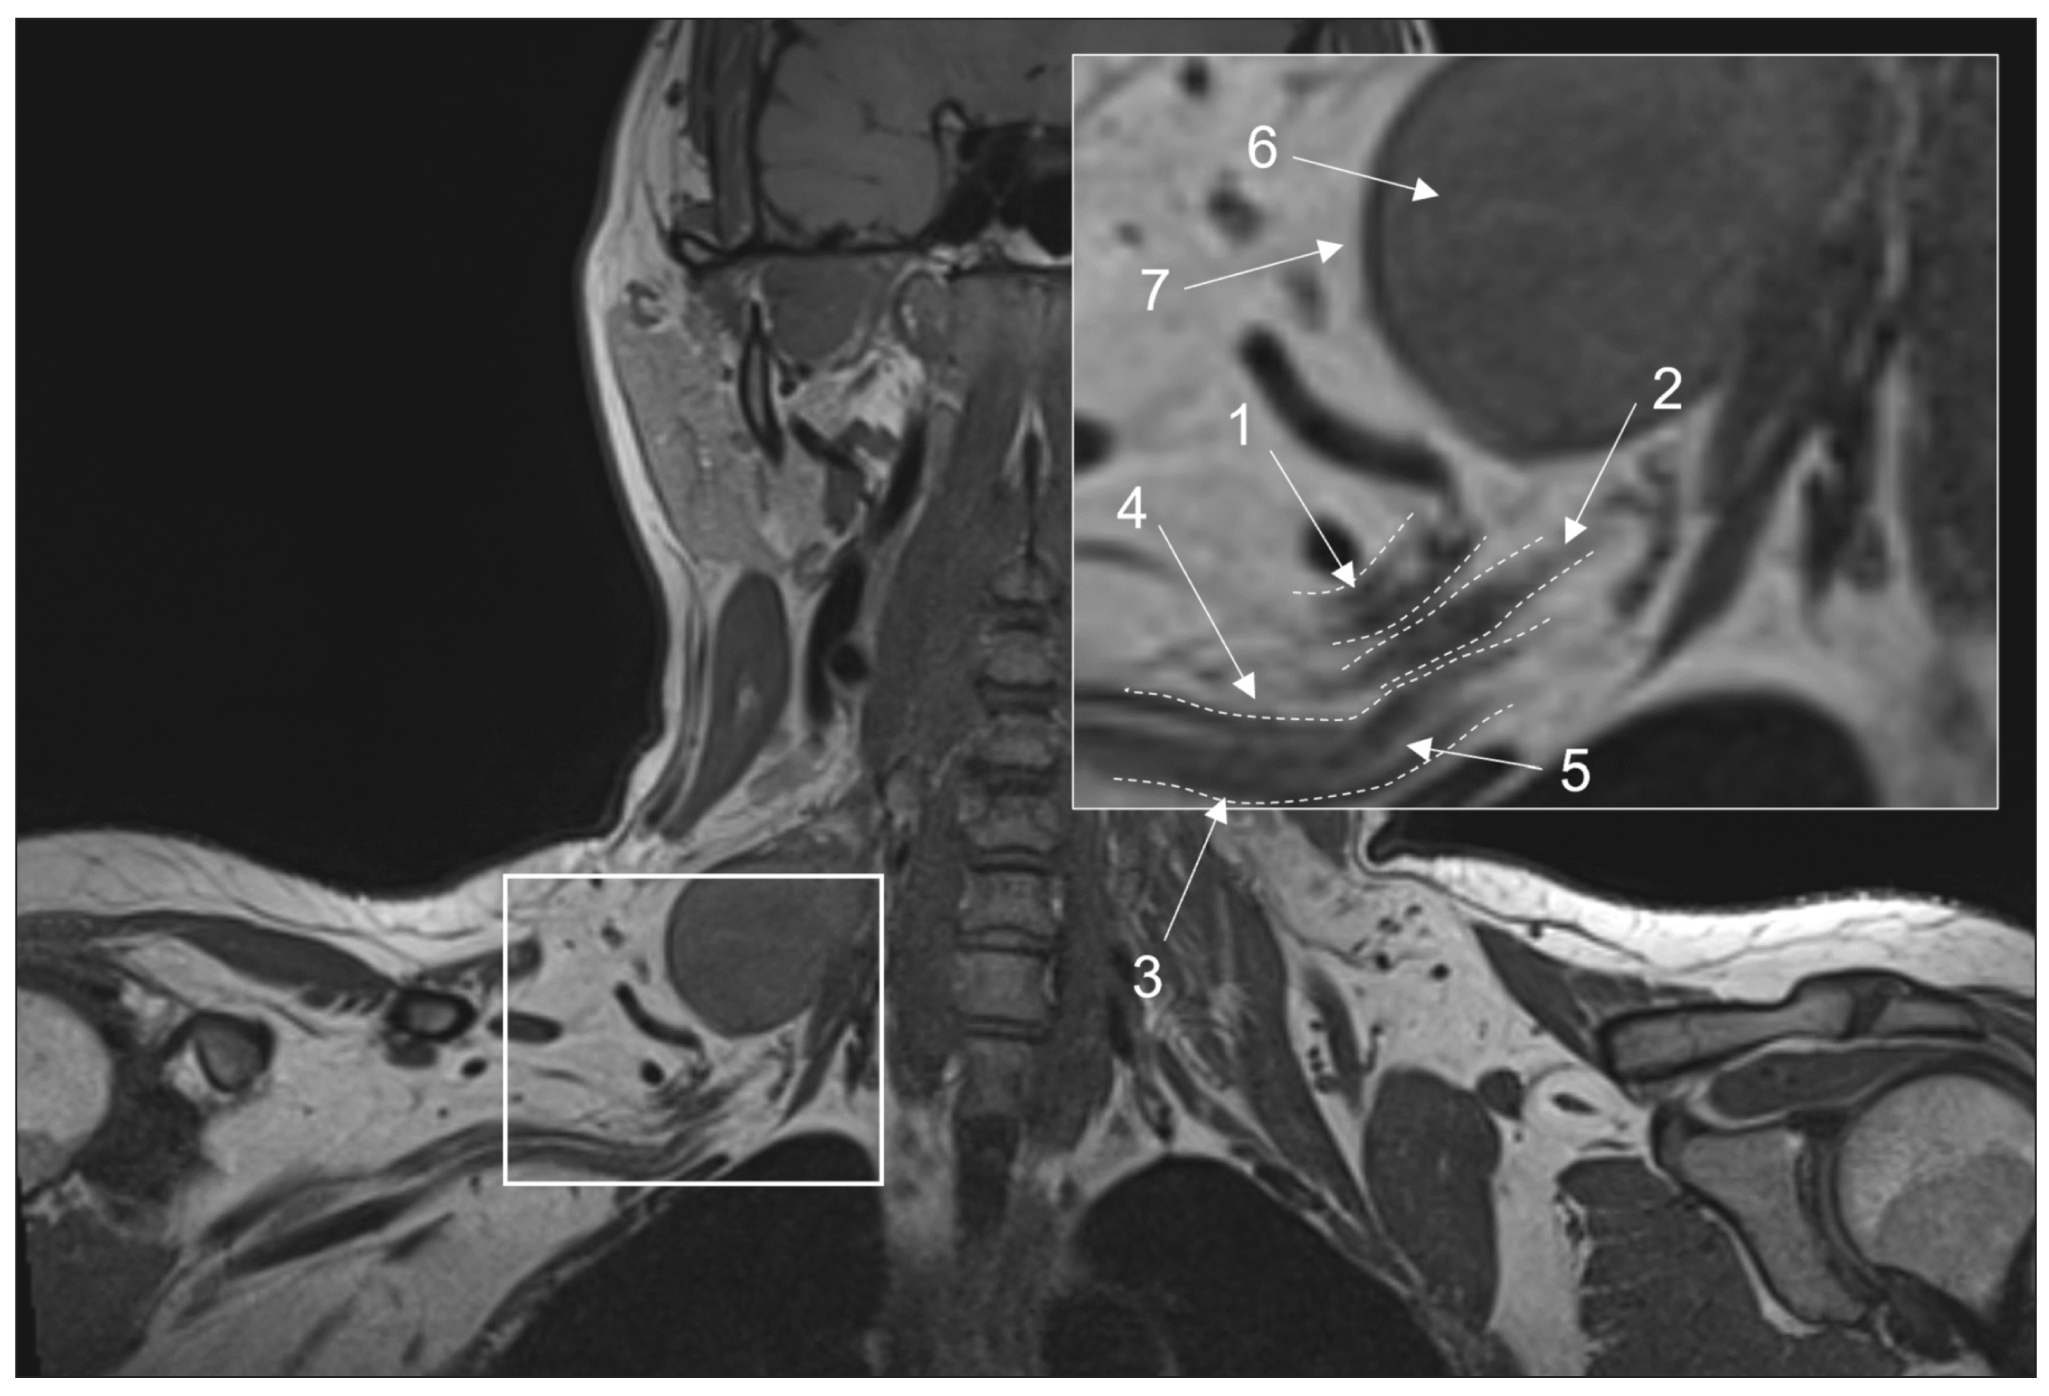

Peripheral neuropathy is known to be one of the most common neurological disorders. Despite the great diagnostic value of electroneuromyography and ultrasound, addressing the diagnostics and differential diagnostics of peripheral nerve diseases of different origin could be challenging. In recent years, magnetic resonance tomography has been increasingly used for evaluating cases of suspected or established peripheral neuropathy with excellent results.

This manuscript mainly deals with the advantages and limitations of the aforementioned diagnostic instruments, technical considerations according to different anatomy of peripheral nerves, along with state-of-the-art technical decisions, frequently used magnetic resonance imaging sequences and their diagnostic value based on own observation, and recommendations for contrast enhancement use and different methods of fat suppression.

- Mazal AT, Faramarzalian A, Samet JD, et al. MR neurography of the brachial plexus in adult and pediatric age groups: Evolution, recent advances, and future directions. Exp Rev Med Devices. 2020;17(2):111–122. doi: 10.1080/17434440.2020.1719830

- Szaro P, McGrath A, Ciszek B, Geijer M. Magnetic resonance imaging of the brachial plexus. Part 1: Anatomical considerations, magnetic resonance techniques, and non-traumatic lesions. Eur J Radiol. 2022;20(9):100392. doi: 10.1016/j.ejro.2021.100392

- Chhabra A, Thawait GK, Soldatos T, et al. High-resolution 3T MR neurography of the brachial plexus and its branches, with emphasis on 3D imaging. AJNR Am J Neuroradiol. 2013;34(3):486–497. doi: 10.3174/ajnr.A3287